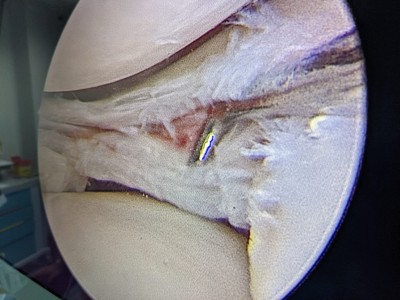

“Pacientul a suferit leziune gravă de menisc extern subluxantă, în langhetă, de corn posterior în totalitate și clivaj orizontal al părții medii meniscale externe. Am efectuat sutura de menisc extern, corn posterior, cu 2 ancore (prin tehnică în lasou) și partea medială, pentru ruptura veche în toartă de coș, ruptă după al doilea traumatism.

Procedura intervențională a fost minim-invazivă (laparoscopică), tehnica de sutură în lasou fiind ceea mai nouă și mai fiabilă (AOSS USA).